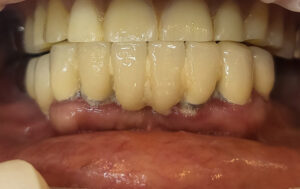

2차 하러 오신 날 최종보철의 형태를 임시치아 재료로 끼고 잘 생활하시다가 3개월 체크할 때 환자분이 편안하다고 하셔서 미리 만들어 놓은 지르코니아 보철로 교체해서 세팅한 모습입니다.

전체 내원 4회로 최종보철의 형태를 임시재료로 끼고 가셨고, 3개월 후 점검할 때 지르코니아로 교체해서 마무리가 되었습니다. 일단 수술 후 5개월째부터는 정상적인 식사가 가능하게 만들어 드렸어요.

전남 고흥에서 오신 60대 여성의 치료가 이렇게 잘 마무리되었고, 치료 끝난 지 1년반 정도되었네요. 1년에 한 번은 오셔서 검진을 해 달라고 부탁드렸어요.